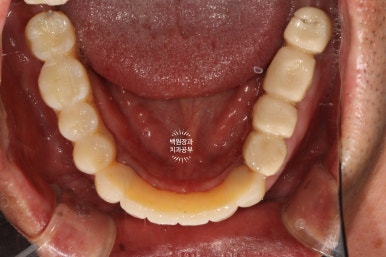

구강내 교합면 사진입니다.

모든 치아가 지르코니아 크라운으로 제작되어, 진짜 자연치같은 형태를 재현해내고 있습니다.

지르코니아 크라운운 캐드캠으로 제작되기 때문에 상당히 자연치와 유사한 형태와 색감을 냅니다.

임상적으로 아주 만족스러운 결과네요.